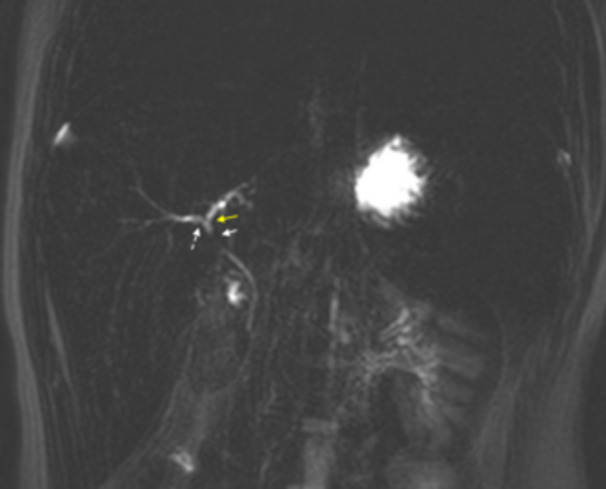

遗传性球形红细胞增多症(HS)患者通常需要红细胞输注治疗溶血性贫血。铁超载是一种已知的频繁输血并发症。一种口服铁螯合剂去铁铁可引起血清转氨酶水平的短暂升高。有一些病例显示镰状细胞性贫血和地中海贫血患者的去铁霉素相关肝损伤。在这个病例报告中,我们提出了一个13岁的男性与输注依赖的HS与去铁宁治疗谁提出了黄疸,并被发现有急性肝细胞损伤的证据。

Patients with hereditary spherocytosis (HS) often require red blood cell transfusions for the treatment of hemolytic anemia. Iron overload is a known complication of frequent transfusions. Deferasirox, an oral iron chelator, can cause transient elevations in serum aminotransferase levels. There have been a few cases demonstrating Deferasirox-associated liver injury in patients with sickle cell anemia and thalassemia. In this case report, we present a 13-year-old male with transfusion-dependent HS treated with Deferasirox who presented with jaundice and was found to have evidence of acute hepatocellular injury.